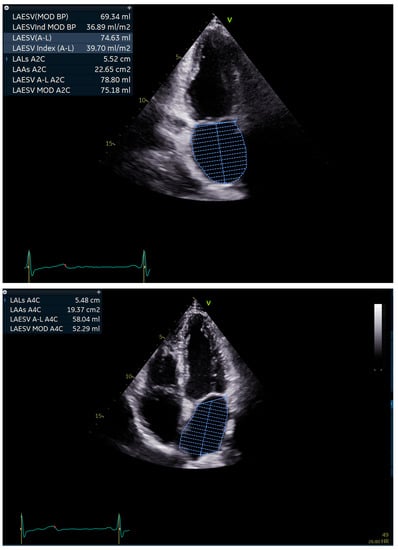

2.2. Echocardiography